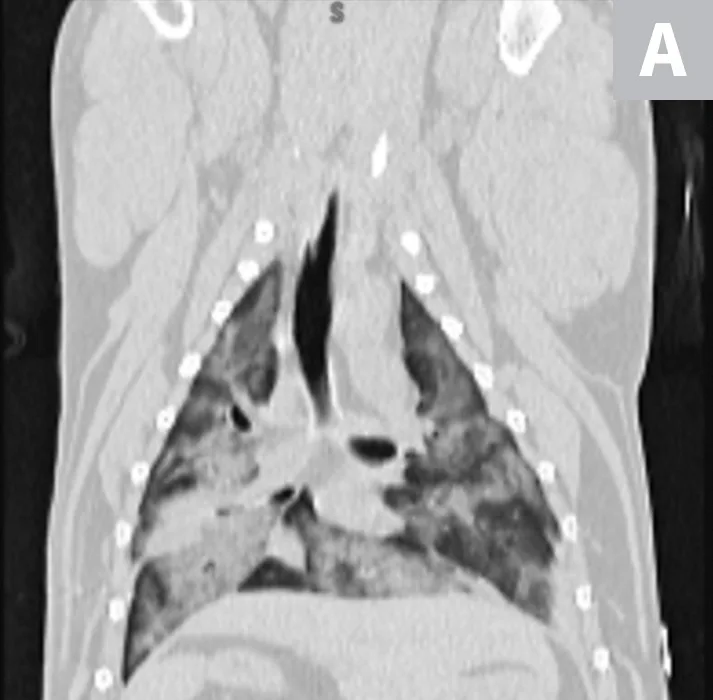

Thoracic CT images of bilateral, diffuse pulmonary infiltrates in a patient with severe trauma secondary to a gunshot wound sustained 24 hours prior to presentation. This patient met 4 criteria for a diagnosis of ARDS (ie, acute onset of respiratory distress, hypoxemia, bilateral diffuse pulmonary infiltrates, known risk factor for trauma).

Evidence of pulmonary capillary leak not due to heart failure or fluid overload (ie, bilateral, diffuse pulmonary infiltrates on thoracic radiographs or CT images)